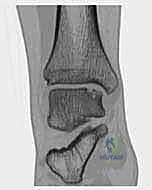

2. التصوير الطبي المتقدم

بما أن الغضاريف لا تظهر بوضوح في الأشعة العادية، يعتمد التشخيص النهائي على تقنيات التصوير المتقدمة:

- التصوير بالرنين المغناطيسي (MRI): هو المعيار الذهبي (Gold Standard) لتشخيص OLTs. يُظهر الرنين المغناطيسي الغضروف بدقة عالية، ويحدد حجم الآفة، عمقها، وحالة العظم تحت الغضروفي (مثل وجود وذمة عظمية - Bone Marrow Edema).

- الأشعة المقطعية (CT Scan): يطلبها الدكتور هطيف أحياناً للحصول على خريطة ثلاثية الأبعاد دقيقة للعظم، مما يساعد في التخطيط الجراحي وتحديد حجم الرقعة العظمية المطلوبة للزرع.